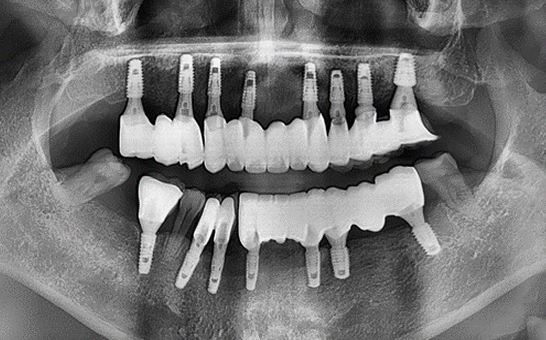

바른선택치과의원 전악 임플란트

치료 시작 전 촬영 2024.01.24 | 치료 완료 후 촬영 2024.12.26

CASE 01 김** / 60대

전악임플란트

1 예후불량 치아 발치

2 발치 후 즉시 임플란트 식립 및 뼈이식

3 고정성 보철물로 수복 후 일상 회복